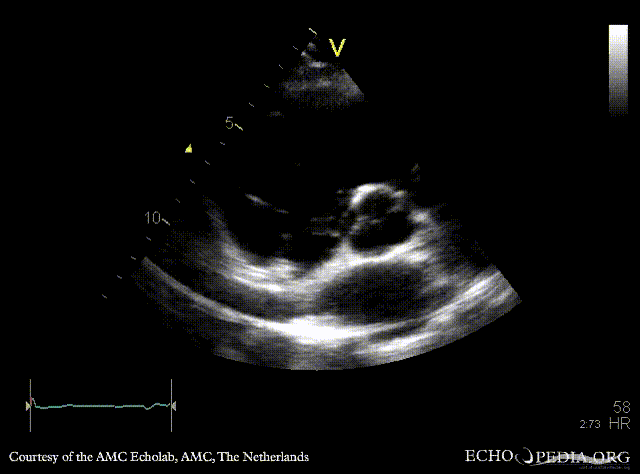

Case 48